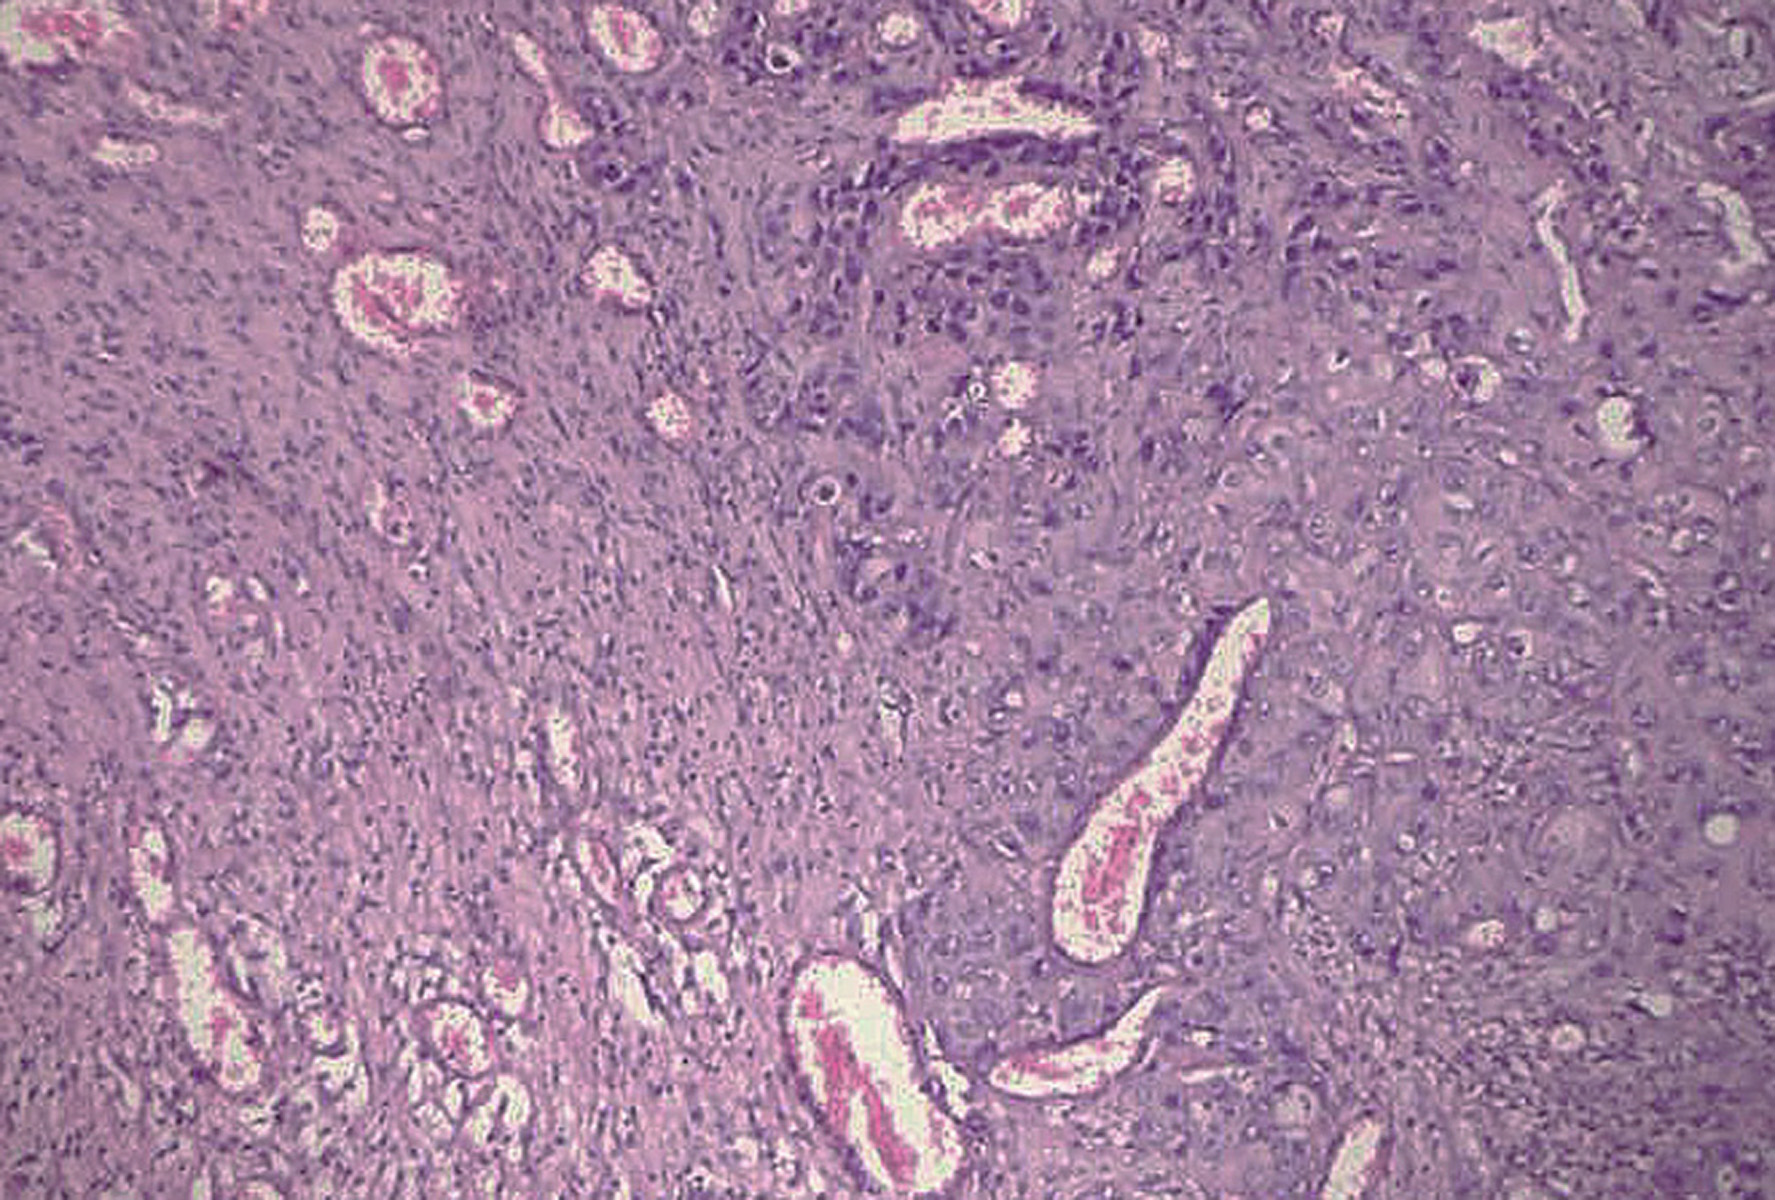

Spread of squamous cell carcinoma (SCC) commonly occurs vialocal lymphatic channels. Owing to scanty lymphatic drainage and vascular supply, SCC arising from the glottis rarely metastasizes. A 39-year-old male, operated for SCC of the glottis, presented 13 months later with complaints of headache. Computed tomography revealed a single ring-enhancing lesion in the right temporo-parietal region of the brain, suggestive of brain abscess. However, histopathological examination of the excised brain lesion showed metastasis of moderately differentiated SCC. Here, we report a rarecase of distant hematogenous brain metastasis of SCC of the glottis.